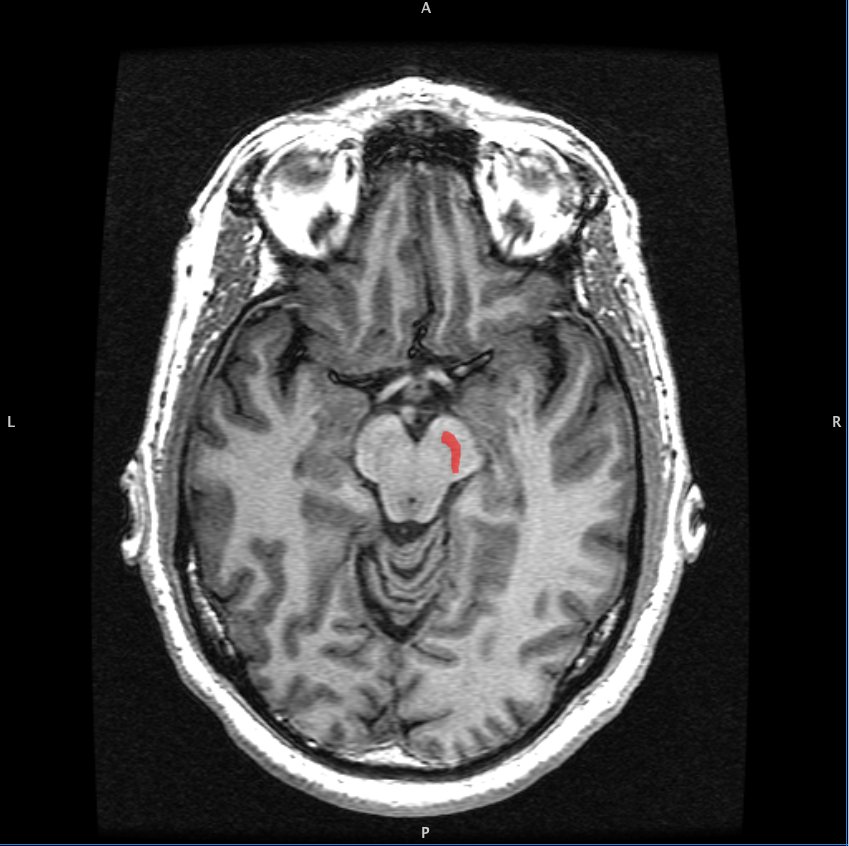

Figure 1: The substantia nigra (SN) nucleus in the midbrain.

Parkinson’s disease (PD) is an age-related, neurodegenerative movement disorder that causes a progressive loss of motor control. The disease is characterized by a loss of dopaminergic (DA) neurons in the substantia nigra (SN), a midbrain nucleus that modulates movement and reward functions. The SN is one of five subcortical nuclei that make up a network called the basal ganglia (BG). This network is in turn connected to other regions of the brain, including the cerebellum, thalamus, and primary motor cortex (M1), that together form the motor pathway responsible for our voluntary movements. The M1 is the output center of this pathway: it signals commands to muscles after its pyramidal neurons receive excitatory DA inputs from regions like the BG, and is regulated by surrounding inhibitory cells in the pathway known as parvalbumin-expressing (PV+) cells. Previous studies have shown reduced activation of M1 in PD patients, prompting questions about the impact of changes in M1’s input-output function.

[2] Image retrieved from: https://en.m.wikipedia.org/wiki/File:Substantia_Nigra.jpg